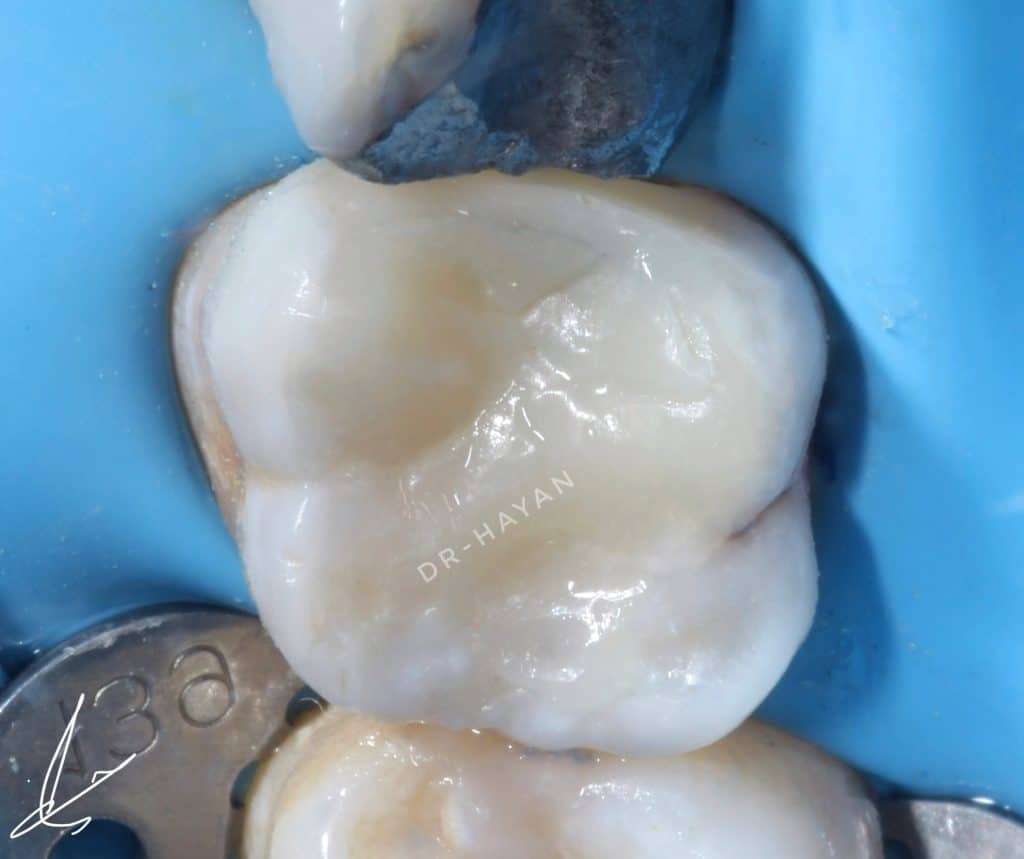

Initial view : 27 years old man suffered from sharp pain related to upper posterior area

Before finishing

After finishing and polishing

Lateral view

After rubber dam removal and extra polishing